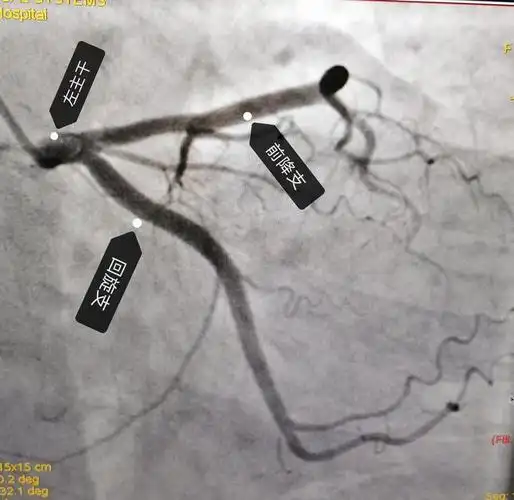

心脏循环有没有狭窄,下面这张图是一个有糖尿病,高血压的患者做的造影

冠脉造影提示:左冠状动脉的前降支也有重度狭窄